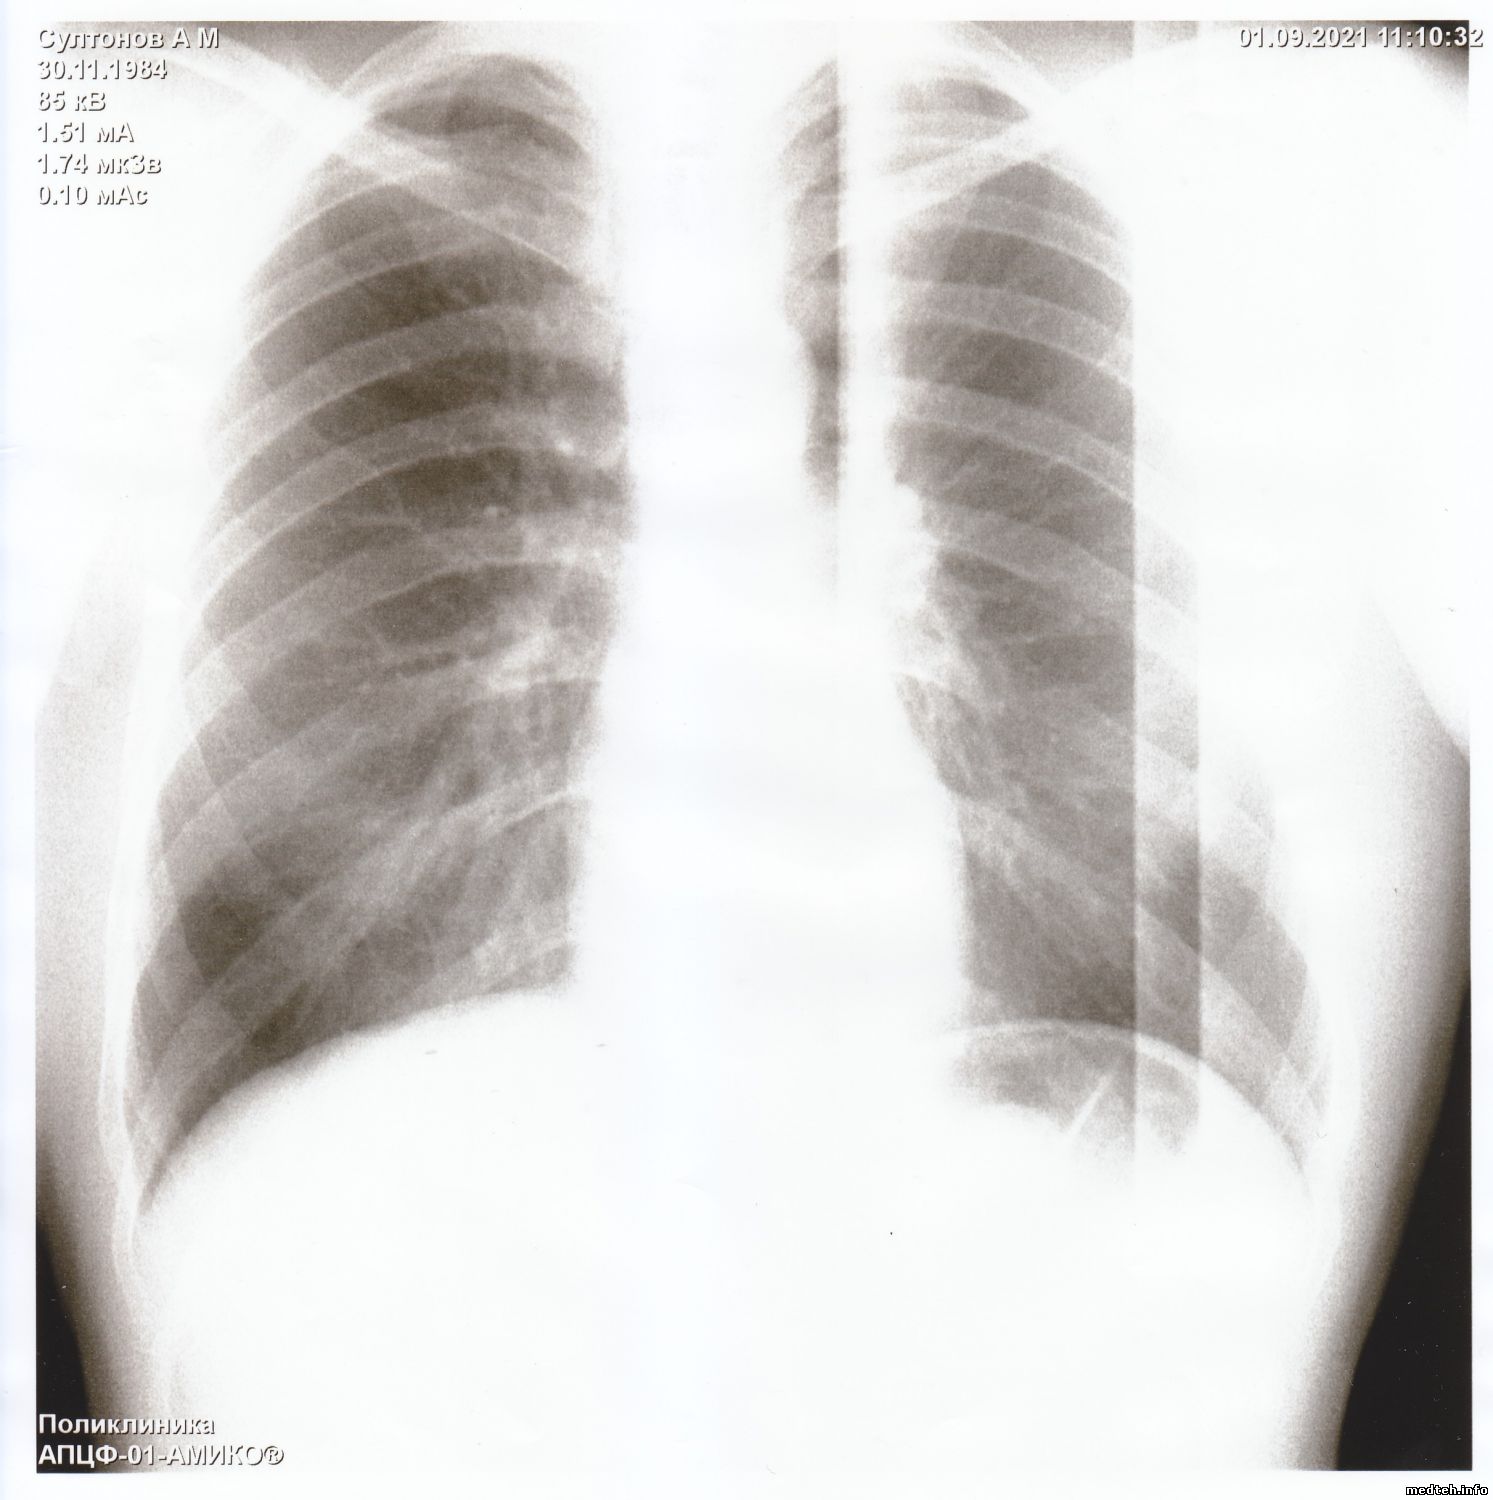

Здравствуйте коллеги.

Прислали снимки из другого города, просят помочь устранить неисправность.

Аппарат я не видел. По снимкам, конечно, не установишь причину, может у кого была такая проблема.

Появились горизонтальные и вертикальные полосы на снимках, делает снимки - смещённые на половину. Снимок есть, видны легкие и все остальное, но полосы очень мешают докторам.

Подскажите что можно сделать в данной ситуации.

Друзья, думаю, вы знаете решение этой проблемы.

Фото прилагается.

Всё решилось просто - тренировка - калибровка и нормальные снимки.